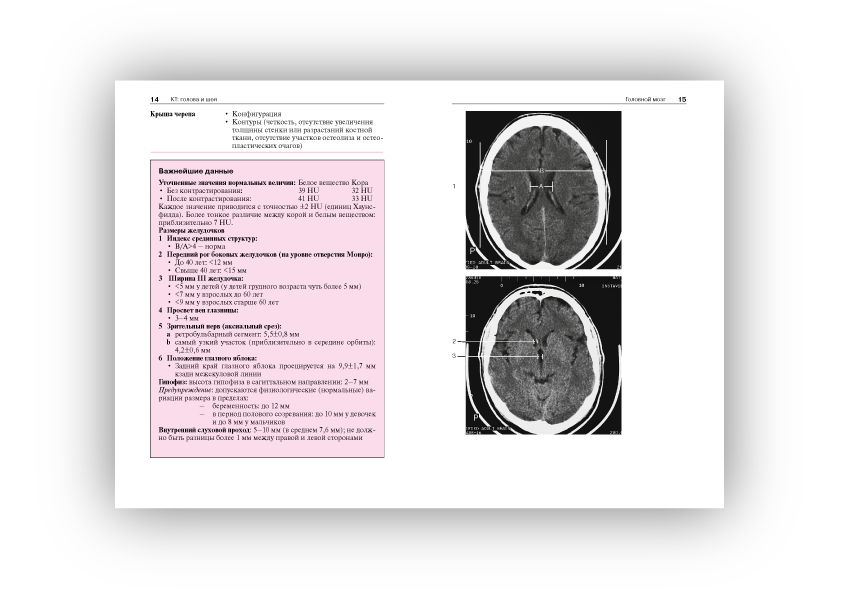

Норма при КТ- и МРТ-исследованиях: пер. с англ./ Торстен Б. Мёллер, Эмиль Райф; под общ. ред. Г.Е.Труфанова, Н.В.Марченко.- 3-е изд. - М.: МЕДпресс-информ, 2016. - 255, [1] с.: ил..

Широкое использование в современной клинической практике компьютерной томографии и магнитно-резонансной томографии как решающих методов диагностики при многих болезнях, относящихся к различным клиническим специальностям и разным анатомическим областям, выдвигает на первый план проблему границ между нормой и патологией при трактовке изображения на срезах.

Помочь врачу - специалисту, составляющему заключение на основании анализа изображений, полученных при КТ- и МРТ-исследованиях, - основная задача этой книги, которая как бы продолжает ранее вышедшую книгу Норма при рентгенологических исследованиях. Каждому из названных методов посвящен самостоятельный ее раздел, охватывающий все исследуемые анатомические области (голова и шея, грудная клетка и т.д.).